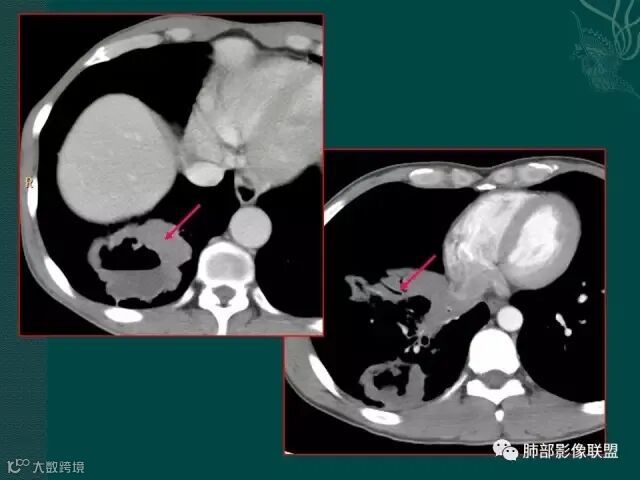

定要记住,在免疫力低下,或白细胞降低的病人,如果在化疗过程中出现痰中带血,最大可能不是肿瘤进展,也不是侵犯血管,而是侵袭性的肺曲霉菌感染。

该病例进展较快,悬球征-霉菌感染的特异征象。